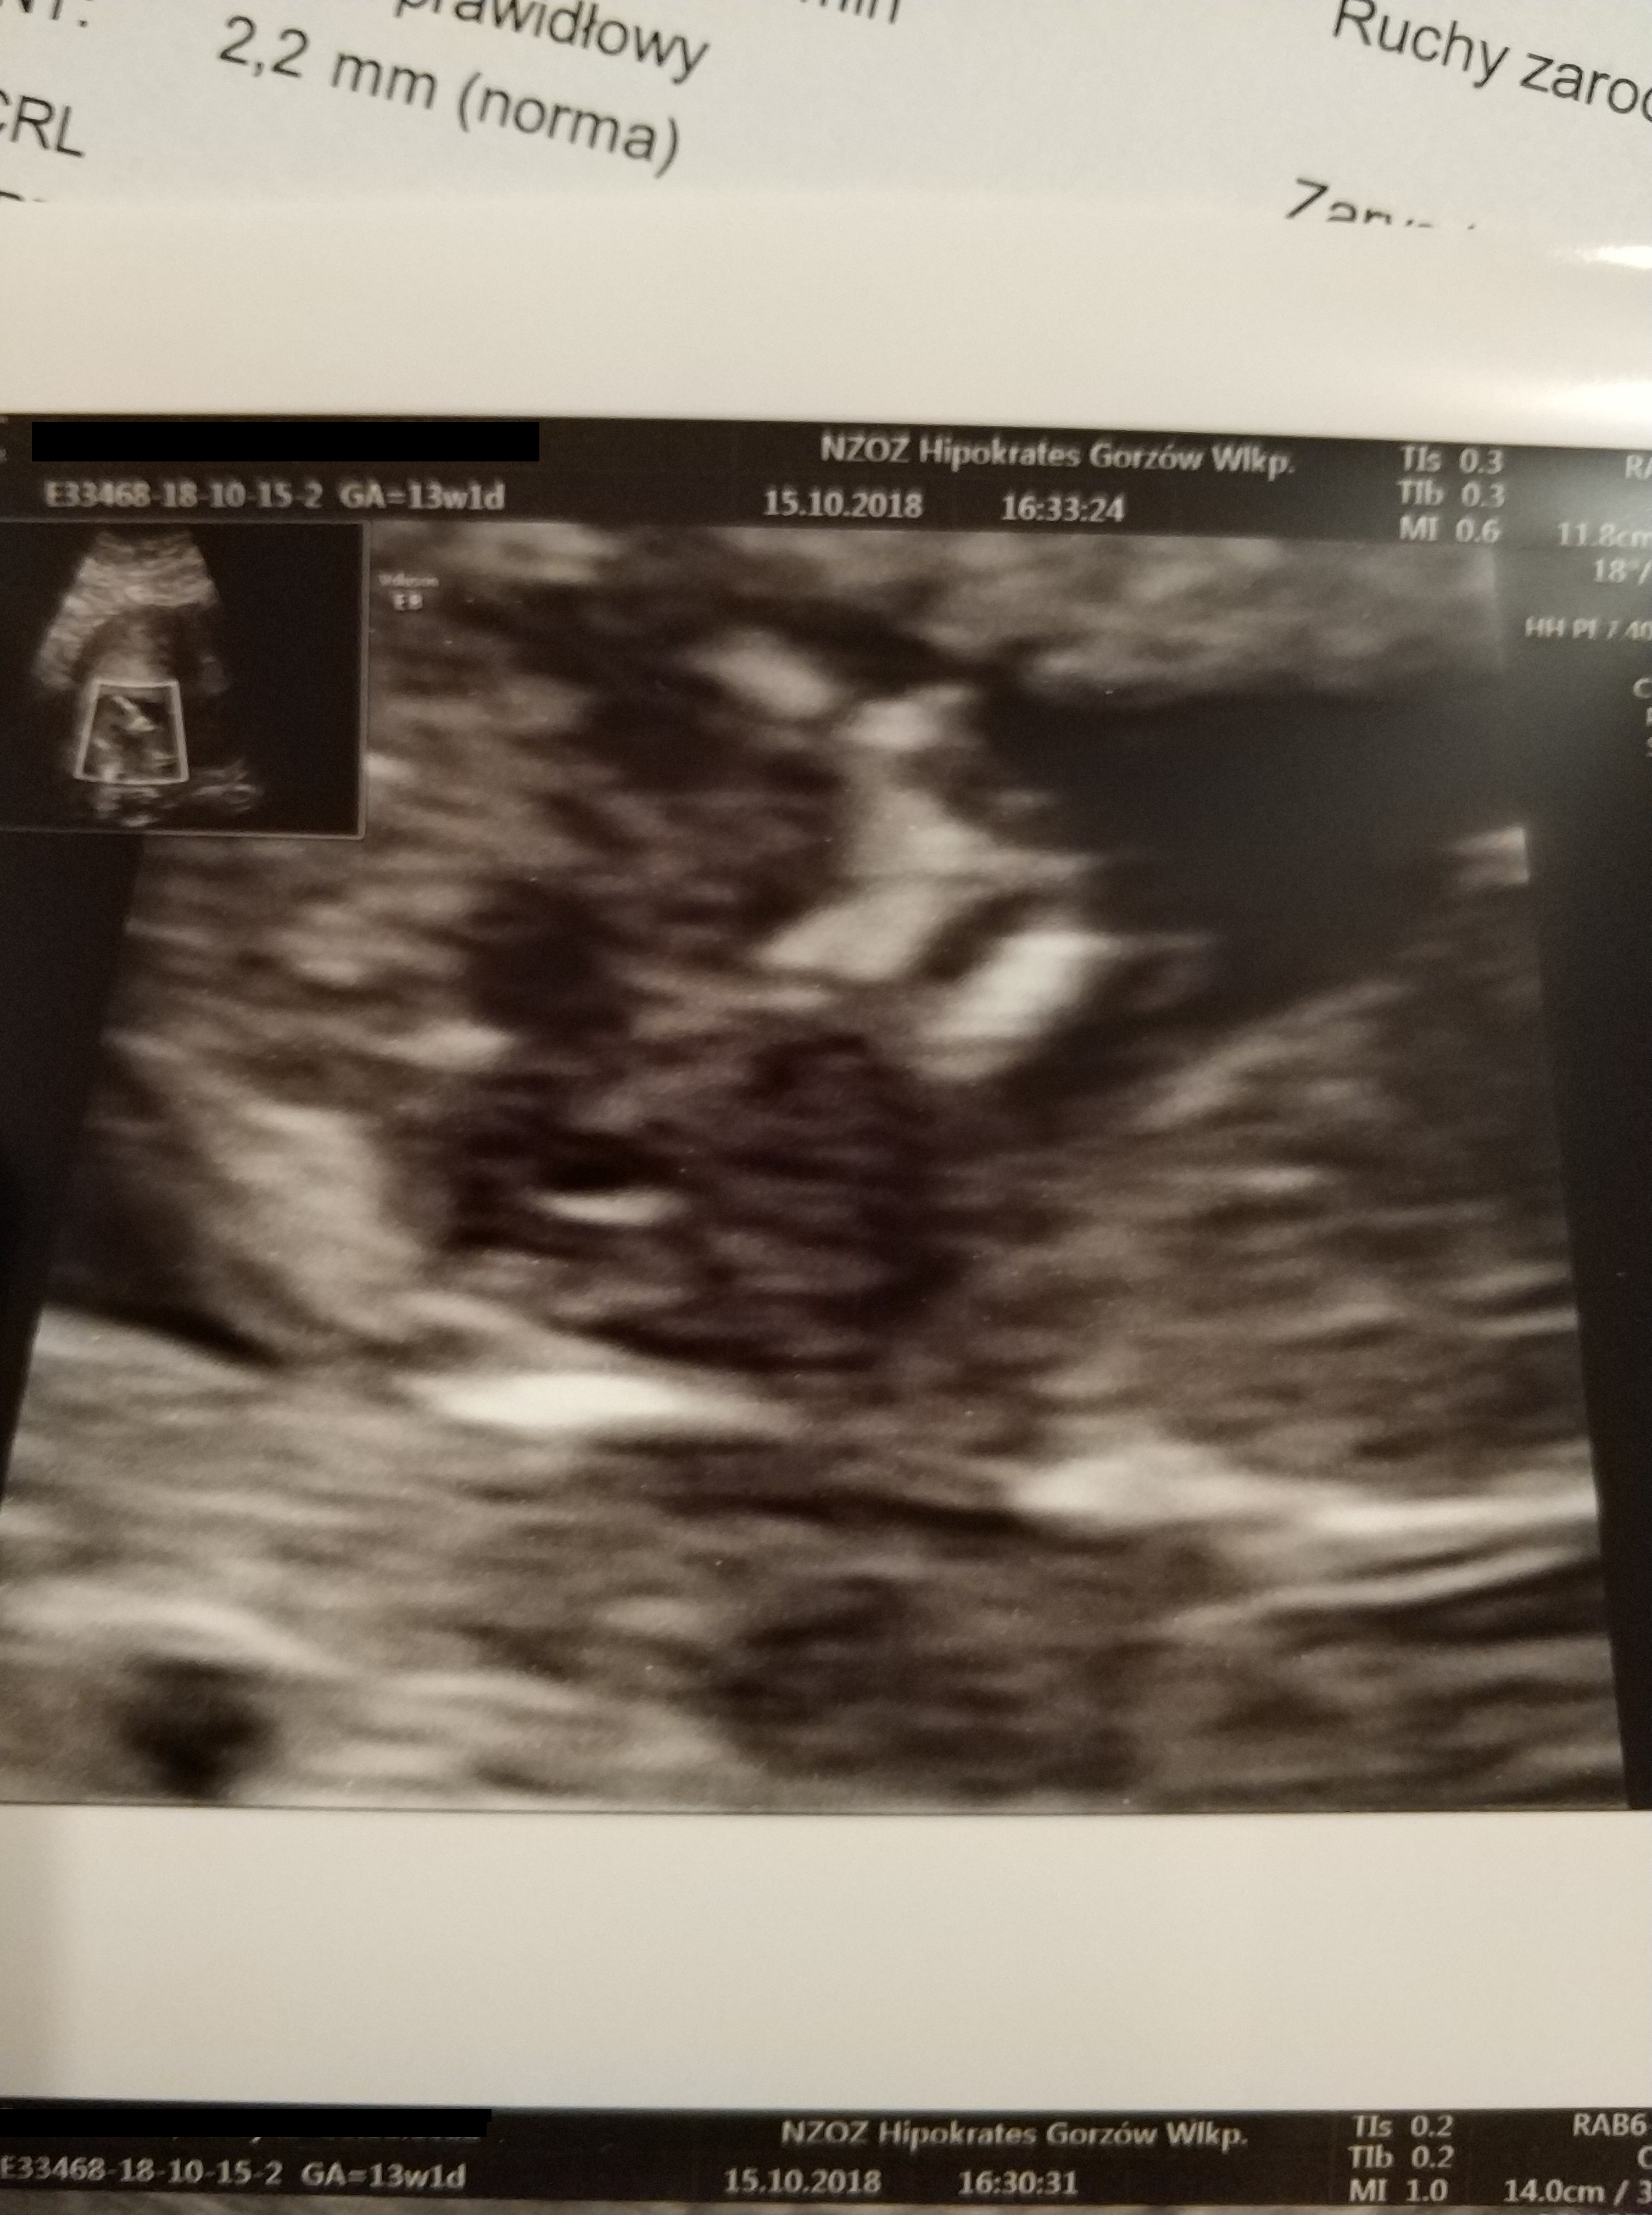

Moje prenatalne wwyszly prawidlowo. dzidzia ma 63mm, odpowiada 12+5, glowka w normie wielkoscia jak z OM 13+1.

serduszko 160u/min w koncu moglam uslyszec!! :)

pecherzyk ciazowy: owalny , NT: 2,2

zarys tułowia: prawidlowy, kosc nosowa: widoczna. Termin porodu 21 kwietnia.

obraz "motyla" mózgu prawidlowy, powloki jamy brzusznej ciagle, cewa nerwowa szczelna, spektrum przeplywu przez zastawkę trojdzielna i przewod zylny - nie do oceny. no i tutaj musze wam powiedziec masa wzruszen byla. dzidzioł tak fikal krecil sie i skakal ze nie szlo go badac. musialam sie obkrecac, kaszlec prowokowac czorta malego.. Pani dr stwierdzila ze niezly skoczek zamieszkuje.

No i prawdopodobnie synek ale mowila zeby jeszcze spokojnie podchodzic do tego.

jestem zadowolona z badania Pani ladnie tlumaczyla, monitor swoj mialam nad glową i wszystko moglam sledzic.

zalaczam kilka fotek :)